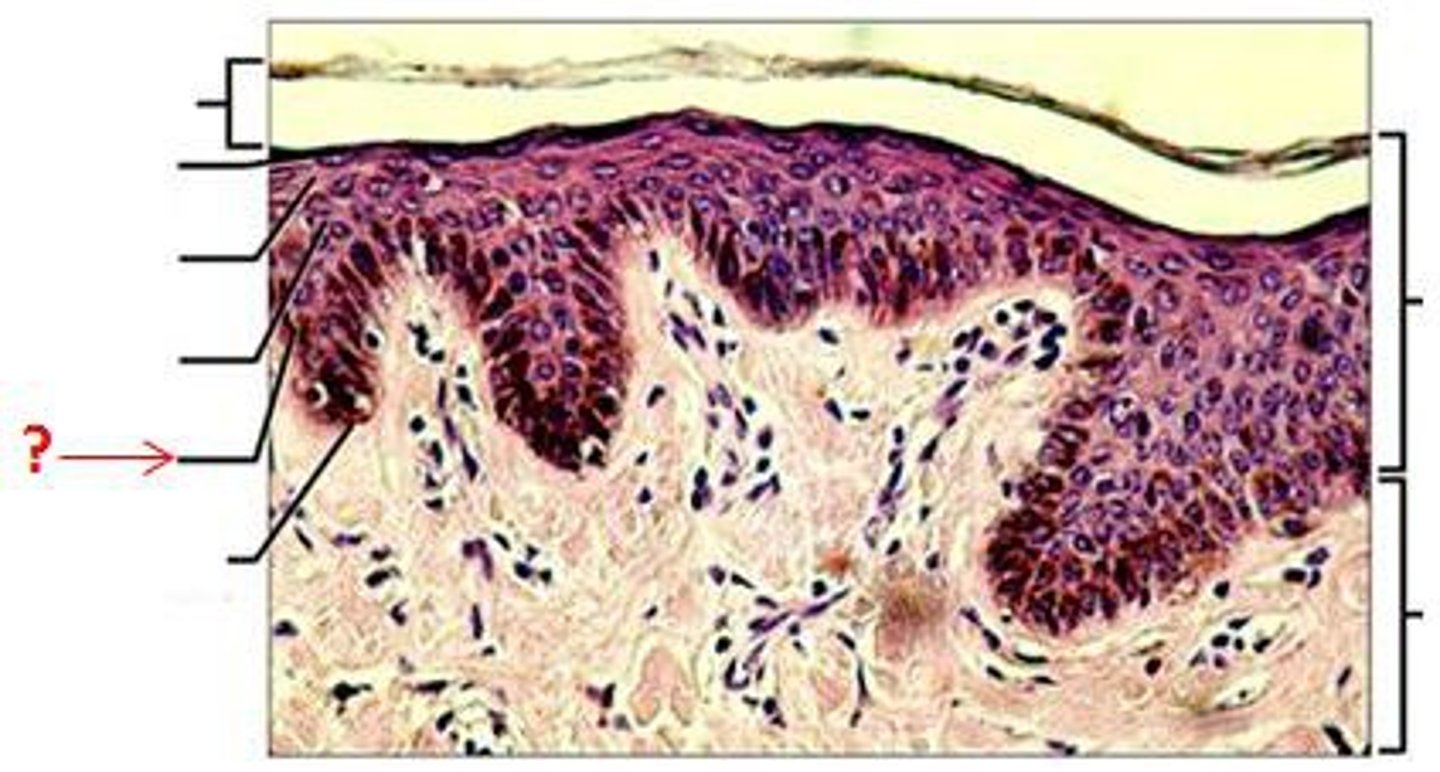

Epidermis

Outer layer of skin

stratum corneum

outermost layer of epidermis

stratum lucidum

Clear, transparent layer of the epidermis under the stratum corneum.

stratum granulosum

a layer of the epidermis that marks the transition between the deeper, metabolically active strata and the dead cells of the more superficial strata

stratum spinosum

stratum basale

the deepest layer of the epidermis consisting of stem cells capable of undergoing cell division to form new cells

Dermis

Inner layer of skin

papillary layer

outer layer of the dermis, directly beneath the epidermis; made of loose connective tissue

reticular layer

The deeper layer of the dermis that supplies the skin with oxygen and nutrients; made of dense irregular connective tissue

dermal papillae

a fingerlike projection of the dermis that may contain blood capillaries or Meissner corpuscles (of touch)